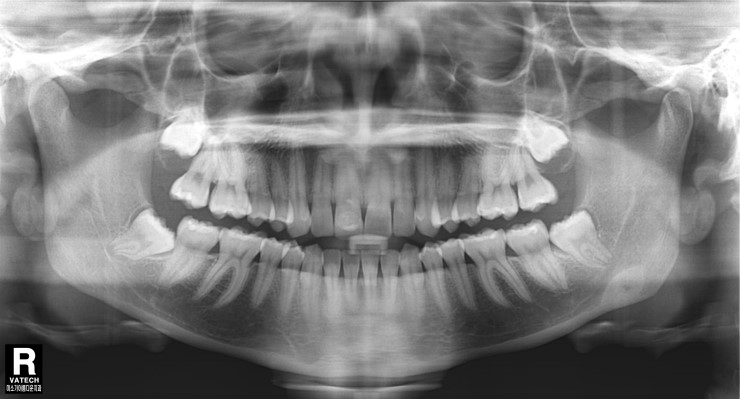

사랑니와 신경관이 붙어 있어 상당히 어려운 케이스입니다.

사진에서 보시는 것처럼 신경관과 사랑니 뿌리가

아주 가까이 붙어 있는 경우에는 상당히 조심을 해야 합니다.

잘못 해서 신경관을 건들기라도 한다면

안면 근육 마비 증세가 오고 한동안 상당히 고생을 할 수 있습니다.

사랑니 뽑기 전 엑스레이 사진입니다.